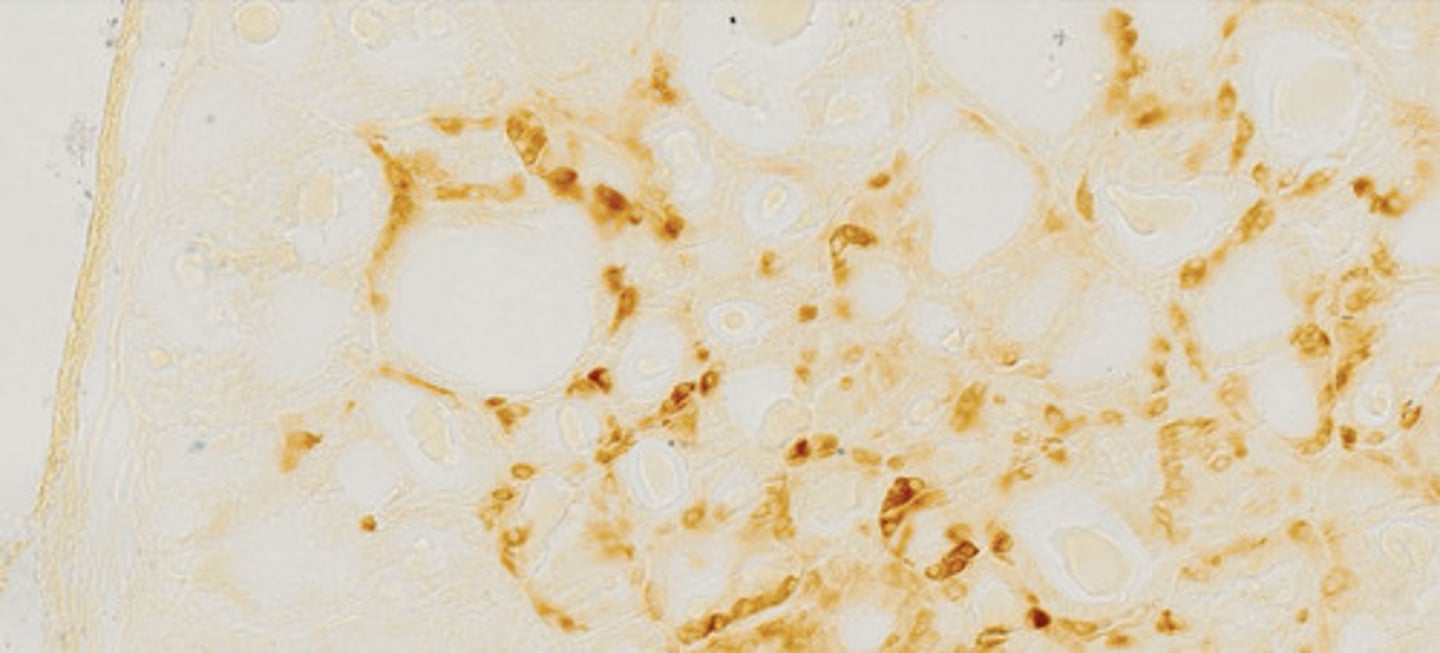

Naczynia włosowate, przedwłosowate i zawłosowate (barw. hematoksylina)

Miąższ płucny (orceina)

Wątroba - komórki Browicza-Kupffera

(barw. błękitem trypanu)